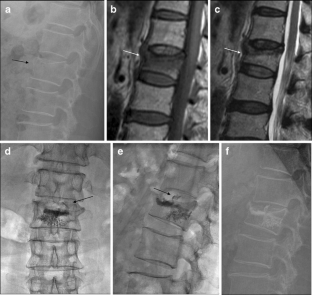

Fig. 1